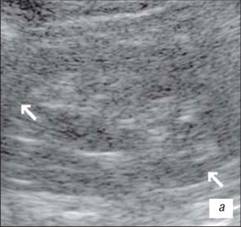

Ехограма нирки

а – запальні зміни в нирці;

б – втягнення на контурі нирки (стрілка)

На данній ехограмі ми помічаємо чіткий патологічний осередок ураження сечоводів, їх розмірів і глибину залягання.